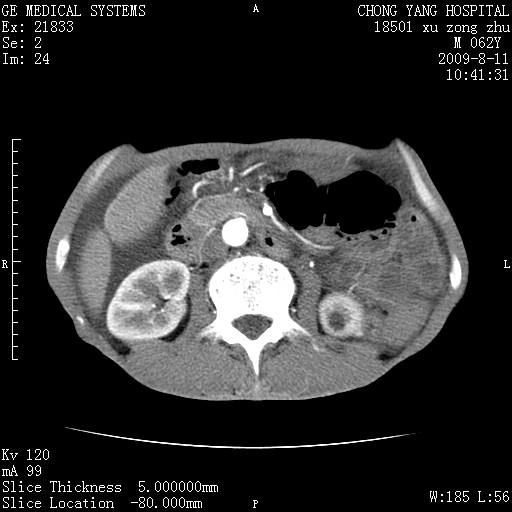

以下是引用杀毒软件在2009-8-11 16:35:00的发言:[br]肝内胆管扩张局限于左叶,胆管内有结石伴肝外胆管结石,胆管壁增厚呈弥漫性并发腹腔积液,胰腺边界模糊。[br][br]考虑---胆总管及肝内胆管结石继发胆管炎及胰腺炎,左肾下极囊肿,腹水。

以下是引用zjzjr在2009-8-11 17:35:00的发言:[br]肝内胆管扩张局限于左叶,胆管内有结石伴肝外胆管结石,胆管壁增厚呈弥漫性并发腹腔积液。[br][br]考虑---胆总管及肝内胆管结石继发胆管炎,左肾下极囊肿,腹水。